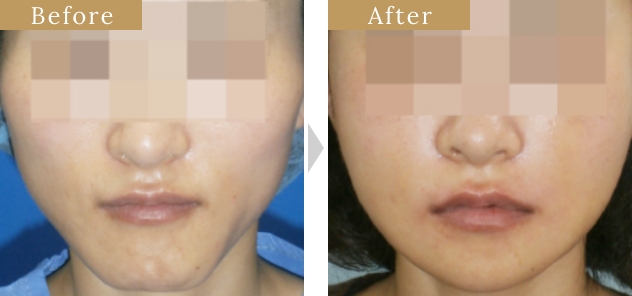

症例

症例